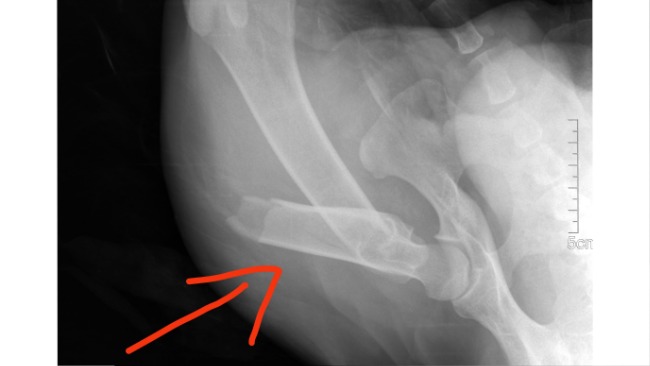

Baloo, bo tak dostał na imię, trafił do schroniska z okropnym złamaniem. Kość udowa w lewej tylnej łapie jest złamana w połowie długości.

Jedynym ratunkiem dla psiaka jest operacja, podczas której kość zostanie usztywniona na metalowej płycie.